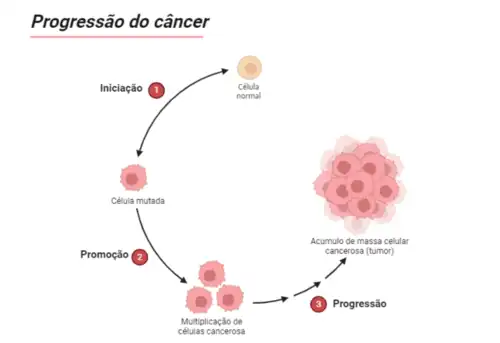

O processo de formação do câncer, denominado carcinogênese ou oncogênese, ocorre lentamente através do acúmulo de mutações, que ao longo do tempo podem resultar na formação de células cancerígenas que proliferam-se dando origem a tumores. O desenvolvimento inicial do câncer ocorre em três estágios, o de iniciação, promoção e progressão do câncer, que estão intrinsecamente relacionados com processos evolutivos como a mutação e a seleção.[28]

A iniciação e a progressão de tumores são considerados processos evolutivos somáticos, impulsionados pelo acúmulo de mutações genéticas, entre as quais podem conferir vantagens de aptidão seletiva à célula hospedeira. [28] Durante a fase de iniciação as células normais sofrem alterações que podem ser provenientes de diversos fatores intrínsecos como mutações genéticas herdadas ou erros aleatórios na replicação do DNA, quanto extrínsecos, por exemplo, a exposição a agentes carcinógenos como radiação, substâncias químicas ou infecções virais, que podem induzir danos e instabilidades genéticas. O desenvolvimento de tumores primários ocorre a partir do acúmulo gradual de mutações ao longo da vida, que podem ser pontuais e neutras ou mutações condutoras de vantagens[28], sendo necessário uma série de modificações genéticas que irão progressivamente agir em genes relacionados aos mecanismos responsáveis por proliferação, diferenciação e morte celular[29]. As mutações resultam em mudanças permanentes no DNA, atingindo principalmente os proto-oncogenes, genes que se mutados podem resultar em crescimento e divisão celular descontrolados, e em genes supressores de tumor, que inibem o crescimento celular descontrolado e promove a reparação do DNA e apoptose.[30]

Durante o estágio de promoção, as células geneticamente alteradas podem sofrer a ação dos oncogenes, ativados pelo acúmulo de mutações, que favorecem a transformação de células normais em cancerígenas, através do crescimento descontrolado de células mutadas.[31] No estágio de progressão tumoral o acúmulo de mutações é intensificado e as células mutadas, agora consideradas pré-cancerígenas, que apresentam vantagens adaptativas em relação às células normais, são selecionadas aumentando o número de subclones com características intensificadas. A seleção das células cancerígenas ocorre no interior dos tecidos do corpo, que evolutivamente adquiriram mecanismos para prevenir o crescimento descontrolado de células anormais, como as cancerígenas, e garantir o funcionamento eficiente do organismo através de propriedades fenotípicas, que se desreguladas podem induzir ou sustentar a malignidade das células cancerosas, levando ao desenvolvimento do câncer.[32] As propriedades fenotípicas podem ser adquiridas através de alterações mutacionais e epigenéticas, sendo as principais a auto-renovação celular, que consiste na capacidade das células se dividirem e renovarem indefinidamente, ocorrendo através da inibição dos genes supressores de tumor e ativação de proto-oncogenes que vão permitir o crescimento descontrolado e a sobrevivência das células anormais; e a estabilização dos telómeros que evita o envelhecimento celular e o encurtamento dos telômeros permitindo que a célula continue a replicar-se[33], que permitem a proliferação, a angiogênese, e a migração celular e evitam a morte celular programada.[30]